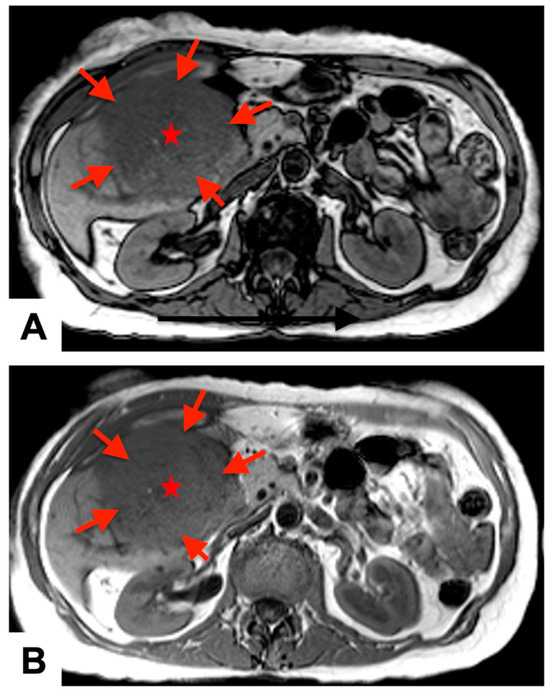

A 74-year-old woman, who had five years prior undergone a partial hepatectomy for hepatocellular carcinoma, was referred to our institution for evaluation of an 8 × 5 × 6 cm3 mass located within the RV. She did not have an elevated alpha-fetoprotein in her history which was negative all the time even prior to hepatic resection and was not treated post-surgical intervention with chemotherapy. In 2018, preoperative magnetic resonance imaging (MRI), demonstrated hepatic mass measuring approximately 13.0 × 10.0 cm2 in size involving posterior segment of the right liver lobe (Figure 1). Her initial surgery for localized HCC had resulted in clear margins; however, surgical report did mention some evidence of vascular invasion. She has been surveilled every 3 months for 2 years, and every 6 months since then with no recurrence. On her recent surveillance in this year, a computed tomography (CT) scan revealed the presence of an RV mass, accompanied by a thrombus within the left brachiocephalic vein after which she was started on apixaban. During this period, she had a significant decline in her exertional tolerance to the point where she had to move around by wheelchair. She developed significant orthopnea and dyspnea on exertion which eventually required her to visit the emergency department.

Figure 1.

Preoperative magnetic resonance imaging: T1 (A) and T2 (B) axial phase views demonstrate a large, heterogeneously enlarging, exophytic hepatic mass (red arrows and stars) in the posterior segment of the right lobe of the liver, measuring approximately 13.0 × 10.0 cm2 in size.